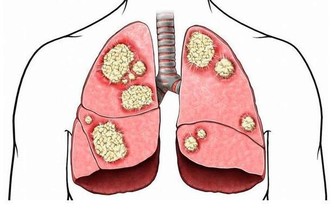

腫瘤部位不同,症狀也不同

同是大腸癌病友,但每個人的情況也會不一樣。

這是因為,長在不同部位的腫瘤,表現出來的症狀不一樣。

升結腸、橫結腸的癌症:症狀更難察覺。這些部位與小腸相連,小腸運來的糞便還處於液態,

即使此處有癌腫出血,出血量也不會太多,肉眼很難觀察到。

但如果出血時間長,會出現貧血,很多人都是出現貧血才發現大腸癌的。

所以,貧血是大腸癌的共同症狀。